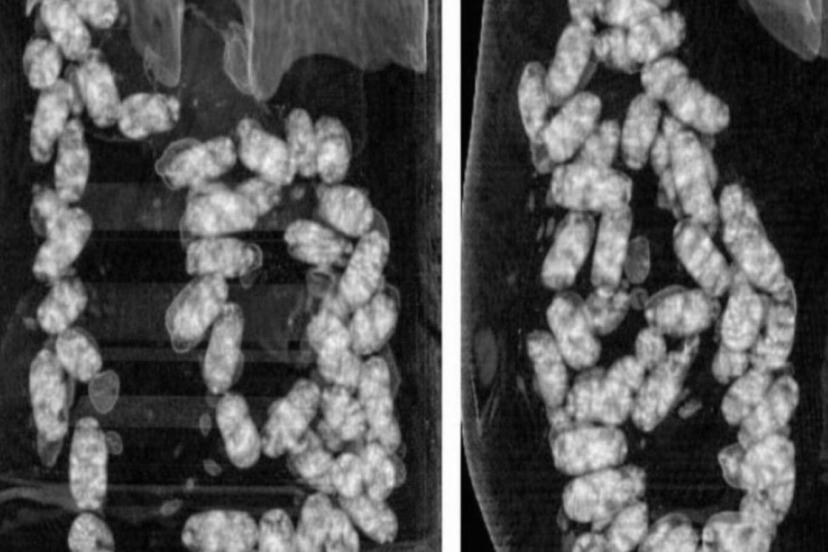

Şüpheliler üzerinde yapılan iç beden muayenesinde, 105 kapsül halinde yutulmuş vaziyette toplam 965 gram metamfetamin ele geçirildi.